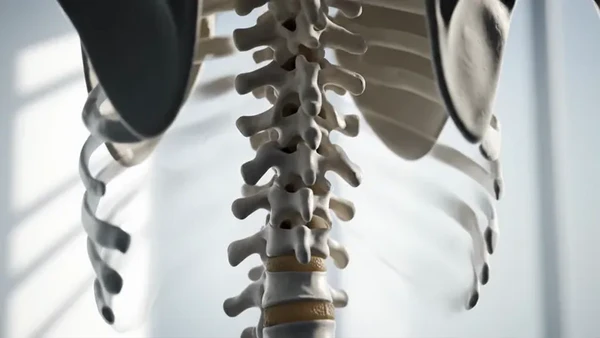

Позвоно́чный столб, или позвоно́чник (лат. columna vertebralis) — основная часть осевого скелета человека. Состоит из 32—33 позвонков, последовательно соединённых друг с другом в вертикальном положении[1][2]. Позвонки разделяют на отдельные типы: шейные, грудные, поясничные, крестцовые (срастаются в крестец) и копчиковые.

Различают 5 отделов позвоночника:

- Шейный отдел (7 позвонков, C1—C7);

- Грудной отдел (12 позвонков, Th1—Th12);

- Поясничный отдел (5 позвонков, L1—L5);

- Крестцовый отдел (5 позвонков);

- Копчиковый отдел (3-4 позвонков)[2], иногда до 5).

Есть 2 вида изгиба позвоночника: лордоз и кифоз. Лордоз — это те части позвоночника, которые выгнуты вентрально (вперед) — шейный и поясничный. Кифоз — это те части позвоночника, которые выгнуты дорсально (назад) — грудной и крестцовый.